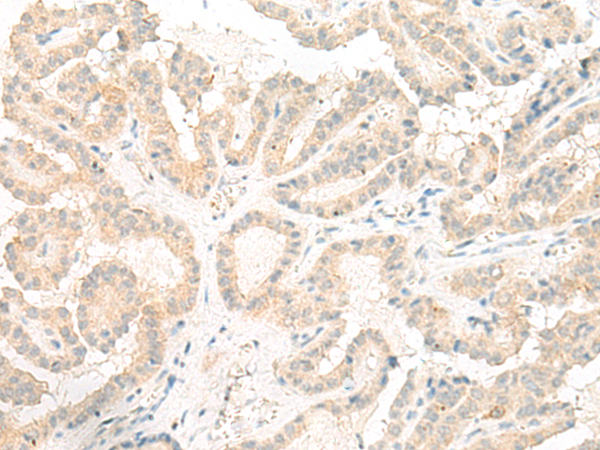

分类: 科研抗体货号: P06594别名: GT01; PGR4; BMIQ10; GPR120; GPR129; O3FAR1应用: IHC反应种属: Human